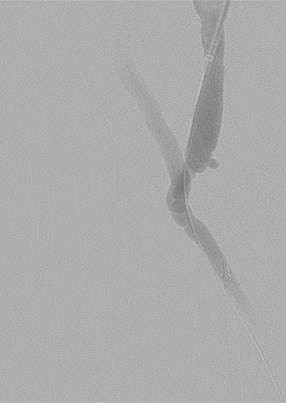

Post 2nd pass with DVX Catheter and balloon angioplasty of underlying stenosis. No impedance to forward flow in AVF.

Once forward flow is established and stenosis treated, the residual thrombus should resolve.